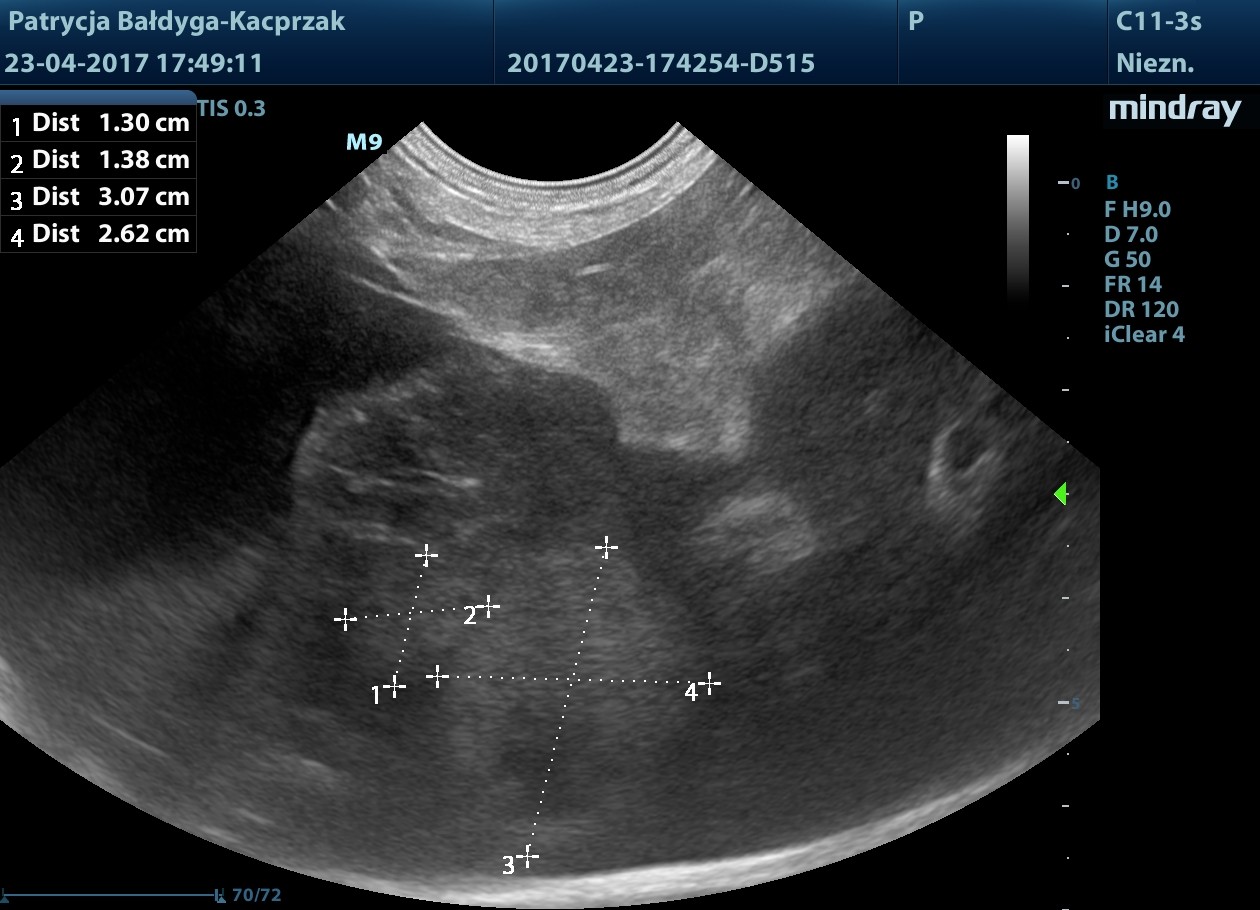

pod pęcherzykiem żółciowym zmiana ok 4,5 cm z drobnymi obszarami hiperechogennymi, jak zwłóknieniowymi/mineralizacyjnymi, gazem?

obrys 1- tu lekki cień akustyczny świadczący o twardości zmiany, obrys 2- tu artefakt rewerberacji, mogący sugerować obecność pęcherzyków gazu